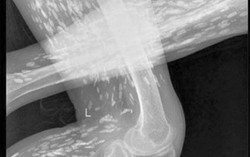

Thực hư cơ thể đầy... gạo khiến dư luận xôn xao

Phòng & chữa bệnh 18:54 09/10/2016Gần đây, dư luận xôn xao và chia sẻ các bức ảnh chụp X-quang một người có đầy gạo tại cơ, xương, khớp… được cho là chụp tại BV Đa khoa TƯ Thái Nguyên. Tuy nhiên, sự thật có như vậy?